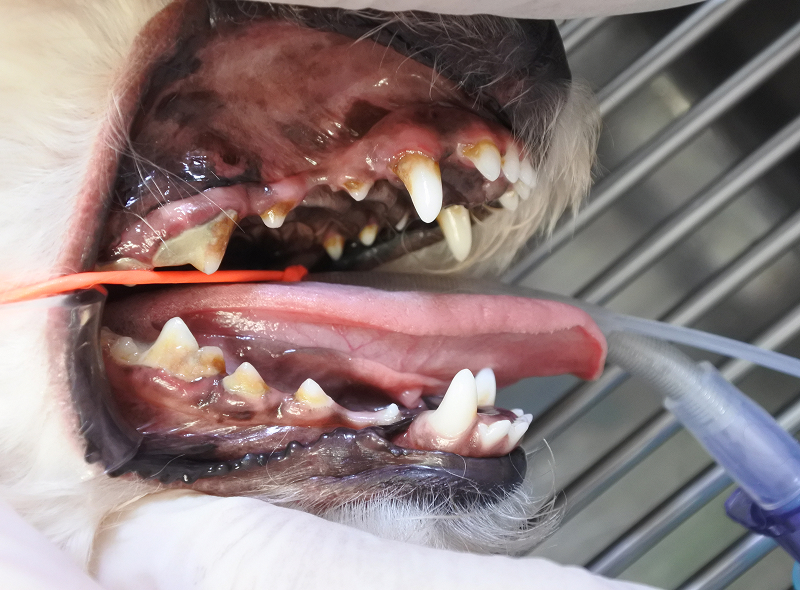

家族の一員として動物たちが認識されていますが、いまだに歯周病にかかっている動物たちは多くいます。あるデータによると3歳以上の犬猫の80%以上は歯周病といわれ、日本においては約1歳以上の小型犬の90%以上は歯周病であるといわれています。

歯周病を飼い主さんが認識していることが少なく、かなり重症化して来院されることが多いです。日常的に歯を見る習慣をつけていただき、また歯磨きの習慣をつけることが重要です。

歯周病治療

歯科疾患として多い病気に歯周病があります。歯周病とは歯垢中の細菌が原因となって歯肉と歯周組織に炎症を起こす疾患です。

初期の歯周病は歯肉のみに炎症を起こします。これを歯周炎と言います。さらに悪化した場合は歯肉の他にセメント質、歯根膜、歯槽骨など歯周組織にまで炎症が及びます。これを歯周炎と言います。歯肉炎と歯周炎を合わせて歯周病と言います。

歯周病治療においては、全身麻酔下で口腔内検査を実施し、歯垢や歯石の蓄積度、歯肉指数、アタッチメントロスの判断、歯周プロービングを実施しプロービングデプスの測定、根分岐部の判断、動揺度の判断を行い、レントゲン検査を実施し、歯周病の診断と重症度の評価を行います。